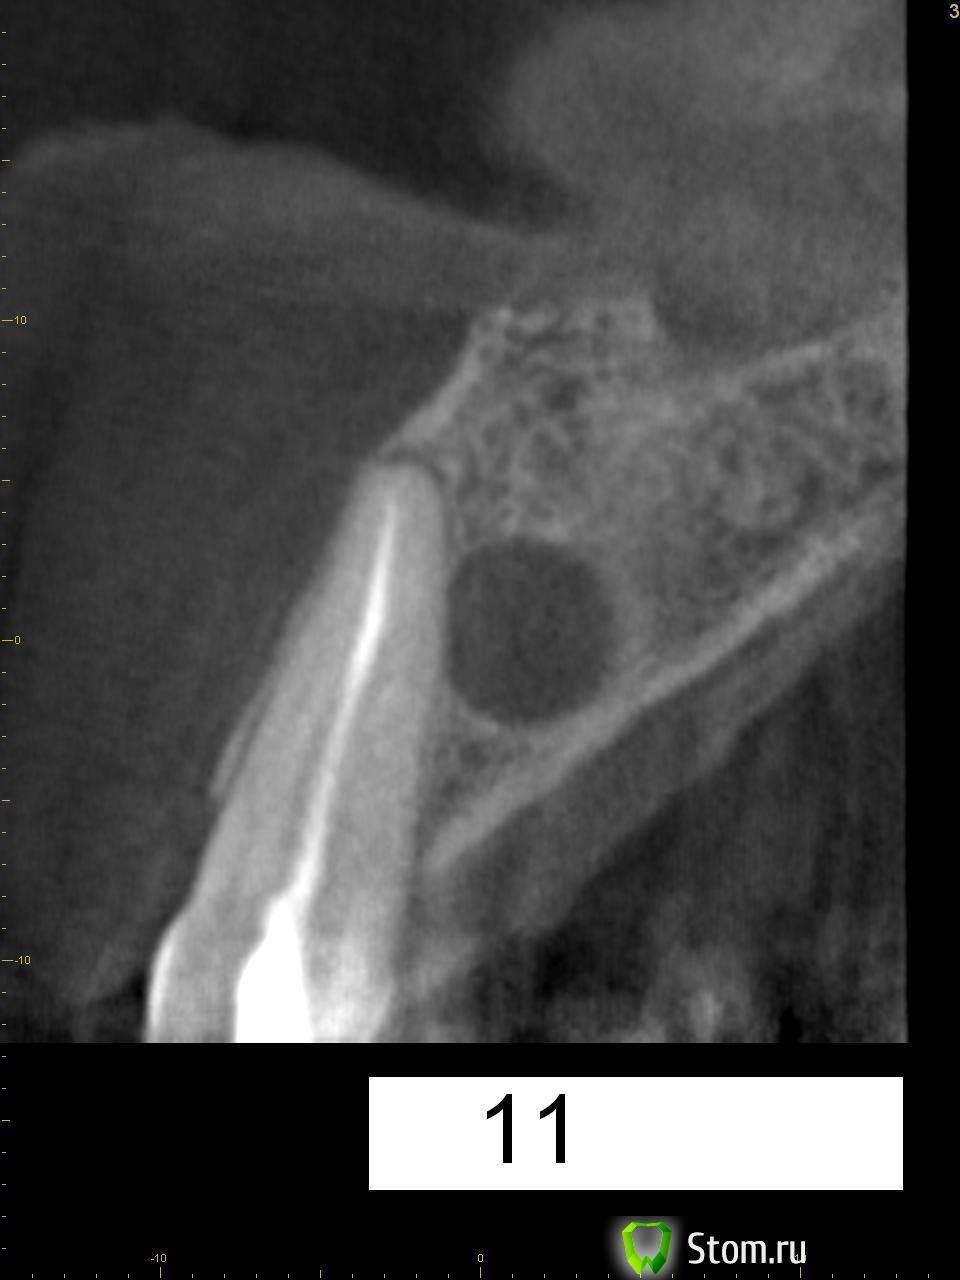

kriokov Опубликовано 20 марта, 2012 Поделиться Опубликовано 20 марта, 2012 Пац 60 лет, 13.03- диагносцирована нагноившаяся киста в\челюсти, вскрыт гнойник, антибактериальная и симптоматическая терапия. На КТ киста до 4 куб см ориентировочно, сквозной дефект с вестибулярной на небную поверхность, деструкция носонебного канала, деструктивный очаг небно за корнем 11. дно носа не критично. Имплантация в перспективе не планируется.Через 1 месяц планируется штатная цистэктомия с удалением 21 и 22. Коллеги, кто как небно мебрану выставляет? Дефект кости на небе 10 на 10 мм. Сам думаю, что под полнослойный лоскут на небе придется устанавливать, попробую отслоиться со стороны костной раны. Ссылка на комментарий

wladdX Опубликовано 22 января, 2014 Поделиться Опубликовано 22 января, 2014 (изменено) Пациентка 33-х лет, обратилась с жалобами на болезненную припухлость на тв. нёбе. При обследовании выявлена киста резцового канала, самопроизвольно вскрывшаяся.Через перф.отверстие отмыта, воспаление стихло, свищевого хода не сформировалось (перф.отверстие эпителизировалось). Встаёт вопрос об операции. Планируется нёбный доступ. Как думаете, коллеги? Изменено 22 января, 2014 пользователем wladdX Ссылка на комментарий